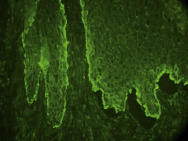

- •

Culture for candidiasis and bacteria or potassium hydroxide preparation (KOH) preparation for fungal elements ( Fig. 3.26 ).

FIG. 3.26

Positive KOH for candidiasis demonstrating an admixture of thin-walled yeast and pseudohyphae.

(Fitzsimons Army Medical Center Collection)